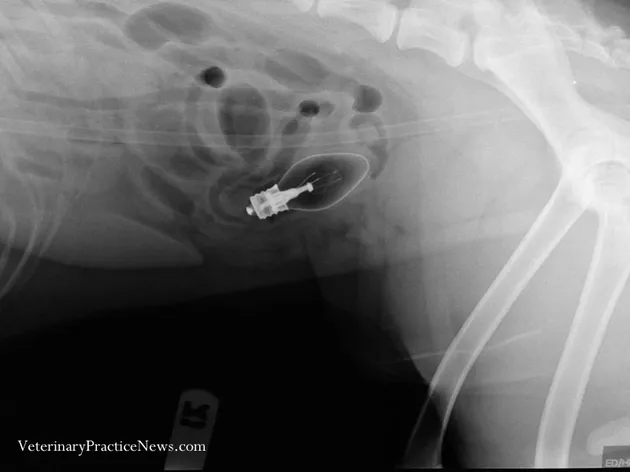

Coby, seekor anjing yang berasal dari Schaumburg selama 2 hari muntah-muntah terus. Pemiliknya yang curiga pun melakukan tes X-Ray, dan ditemukan jika Coby menelan bohlam lampu. Lampu tersebut pada akhirnya bisa dikeluarkan dari perut Coby.

Hak Cipta: Veterinary Practice News